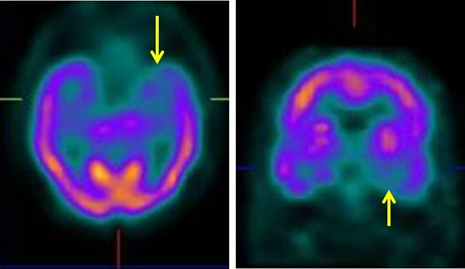

El estudio se realizó mediante inyección endovenosa de 25 mCi (925 MBq) de 99mTc-etil-cisteinato-dímero (ECD), adquiriéndose imágenes tomográficas (SPECT) a los 30 minutos post-administración del trazador. Las imágenes mostraron hipoperfusión temporal izquierda, hallazgo característico de la APP, sin otros cambios significativos en la corteza cerebral, núcleos de la base o cerebelo (figs. 1 y 2).

El hallazgo característico del SPECT y PET en pacientes con APP es la hipoperfusión/hipometabolismo asimétrico predominando en el lóbulo temporal izquierdo(5,6), en contraste con los defectos parietotemporales bilaterales y simétricos de la EA(7). Westbury et al(8) en una revisión de 112 pacientes con APP, de los cuales 59 fueron estudiados con SPECT y PET, encontraron en 97% de ellos anomalías en el flujo sanguíneo cerebral; 69% de los 58 estudios reportados como anormales mostraron alteraciones en el hemisferio izquierdo, mientras que el resto tuvo hipoperfusión bilateral. Sin embargo, se relatan casos de hipoperfusión en el hemisferio no dominante, aunque en forma menos frecuente(9). En nuestro caso, se demostró claramente mediante SPECT una zona hipoperfundida limitada al lóbulo temporal izquierdo sin detectarse cambios sugestivos de encefalopatía vascular o degenerativa de otro tipo, reforzando así el diagnóstico clínico de APP.